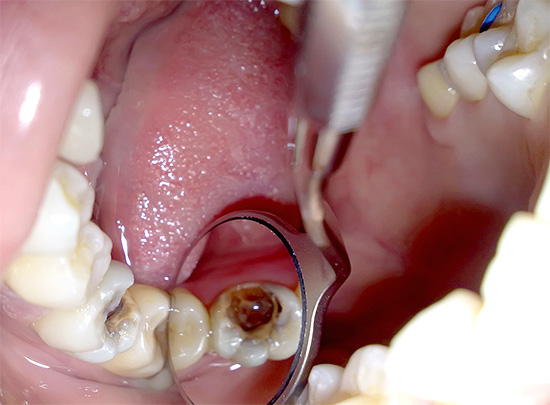

La foto sotto mostra il nervo rimosso dal dente:

La rimozione di un nervo da un dente lo fa diventare "morto" e perde la sua capacità di percepire quasi tutti i tipi di stimoli (freddo, dolce, acido, salato). Ma un dente viene chiamato morto, prima di tutto, per il motivo che perde il suo apporto di sangue, il tasso di processi di mineralizzazione diminuisce significativamente in esso - in altre parole, diventa fragile nel tempo e lo smalto diventa opaco.